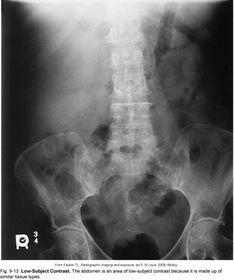

Low-Subject Contrast -similar tissue types - similar shades of gray *ABDOMEN*